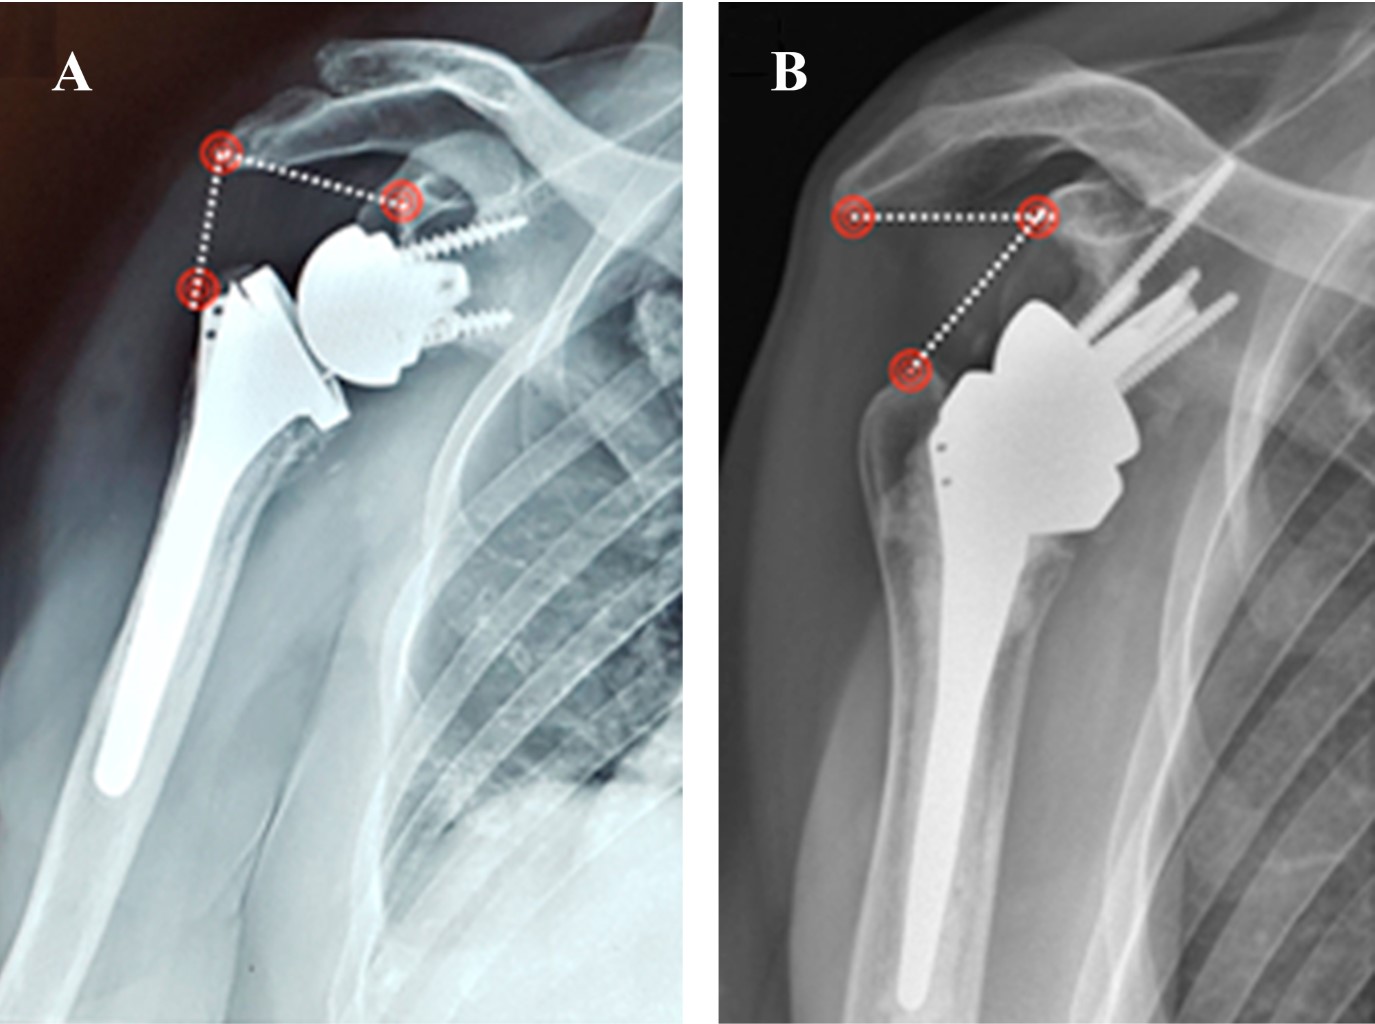

Purpose: Compare functional and radiological outcomes of three different designs of reverse shoulder arthroplasty according to distalization and lateralization shoulder angle, in heterogenic diagnostics (fracture, cuff arthropathy, fracture sequela and osteoarthritis). Material and methods: Prospective cohort of 33 patients of reverse shoulder arthroplasty (RSA) between December 2014 and July 2017 with a minimum one year of follow-up. We defined three groups, G: 10 patients with Grammont (155o, Medialized Glena), B: 9 patients with Bio-RSA (155º, lateralized bone glena) and A: 14 patients with Arrow (135o, lateralized metallic glena). We analyze demographic, clinical, functional and radiological outcomes (lateralization shoulder angle (LSA) and distalization shoulder angle (DSA)). For the statistical analysis, ANOVA, T-tests and linear regression tests were used, with a statistical significance of 5%. Results: The LSA was significantly higher in group A (98o A, 79o G, 80o B) (p < 0.05). In DSA, group B was significantly higher than A (52o B, 39o A) (p < 0.05) and not significant to G (48o G) (p = 0.06). There was no correlation of LSA and DSA with external rotation (p = 0.51) and active elevation (p = 0.41), respectively. There was no significant clinical (anterior elevation, external rotation, internal rotation) and functional outcomes (adjusted Constant score and subjective shoulder evaluation) differences between the different RSA models (p > 0.05). Conclusions: The LSA was higher in the Arrow and the DSA was higher in Bio-RSA. We did not find Clinical - Radiological correlation in this heterogeneous series of patients.

Figure 3